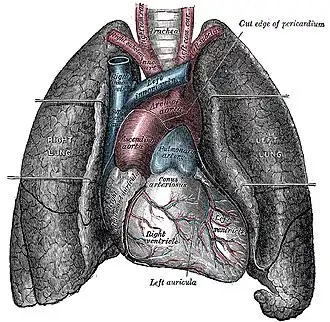

Vista frontal dos pulmões (cortados) | |

Os pulmões humanos são divididos em segmentos denominados lobs (pronuncia-se "lóbos", com a primeira vogal aberta). O pulmão esquerdo possui dois lobs e o direito possui três.[1]

O pulmão direito é mais espesso e mais largo que o pulmão esquerdo, e é também um pouco mais curto, pois o diafragma é mais alto no lado direito para acomodar o fígado.[4] O pulmão esquerdo tem uma concavidade que é a incisura cardíaca.[4]

Os pulmões são compostos de brônquios que se dividem em bronquíolo e alvéolos pulmonares. Os alvéolos totalizam-se em um total de 4 milhões e são estruturas saculares (semelhantes a sacos) que se formam no final de cada bronquíolo e têm em sua volta os chamados capilares pulmonares. Nos alvéolos se dão as trocas gasosas ou hematose pulmonar entre o meio ambiente e o corpo, com a entrada de oxigênio na hemoglobina do sangue (formando a oxiemoglobina) e saída do gás carbônico ou dióxido de carbono dos capilares para o alvéolo.

Nos pulmões os brônquios ramificam-se intensamente, dando origem a tubos cada vez mais finos, os bronquíolos. O conjunto altamente ramificado de bronquíolos é a árvore brônquica ou árvore respiratória.